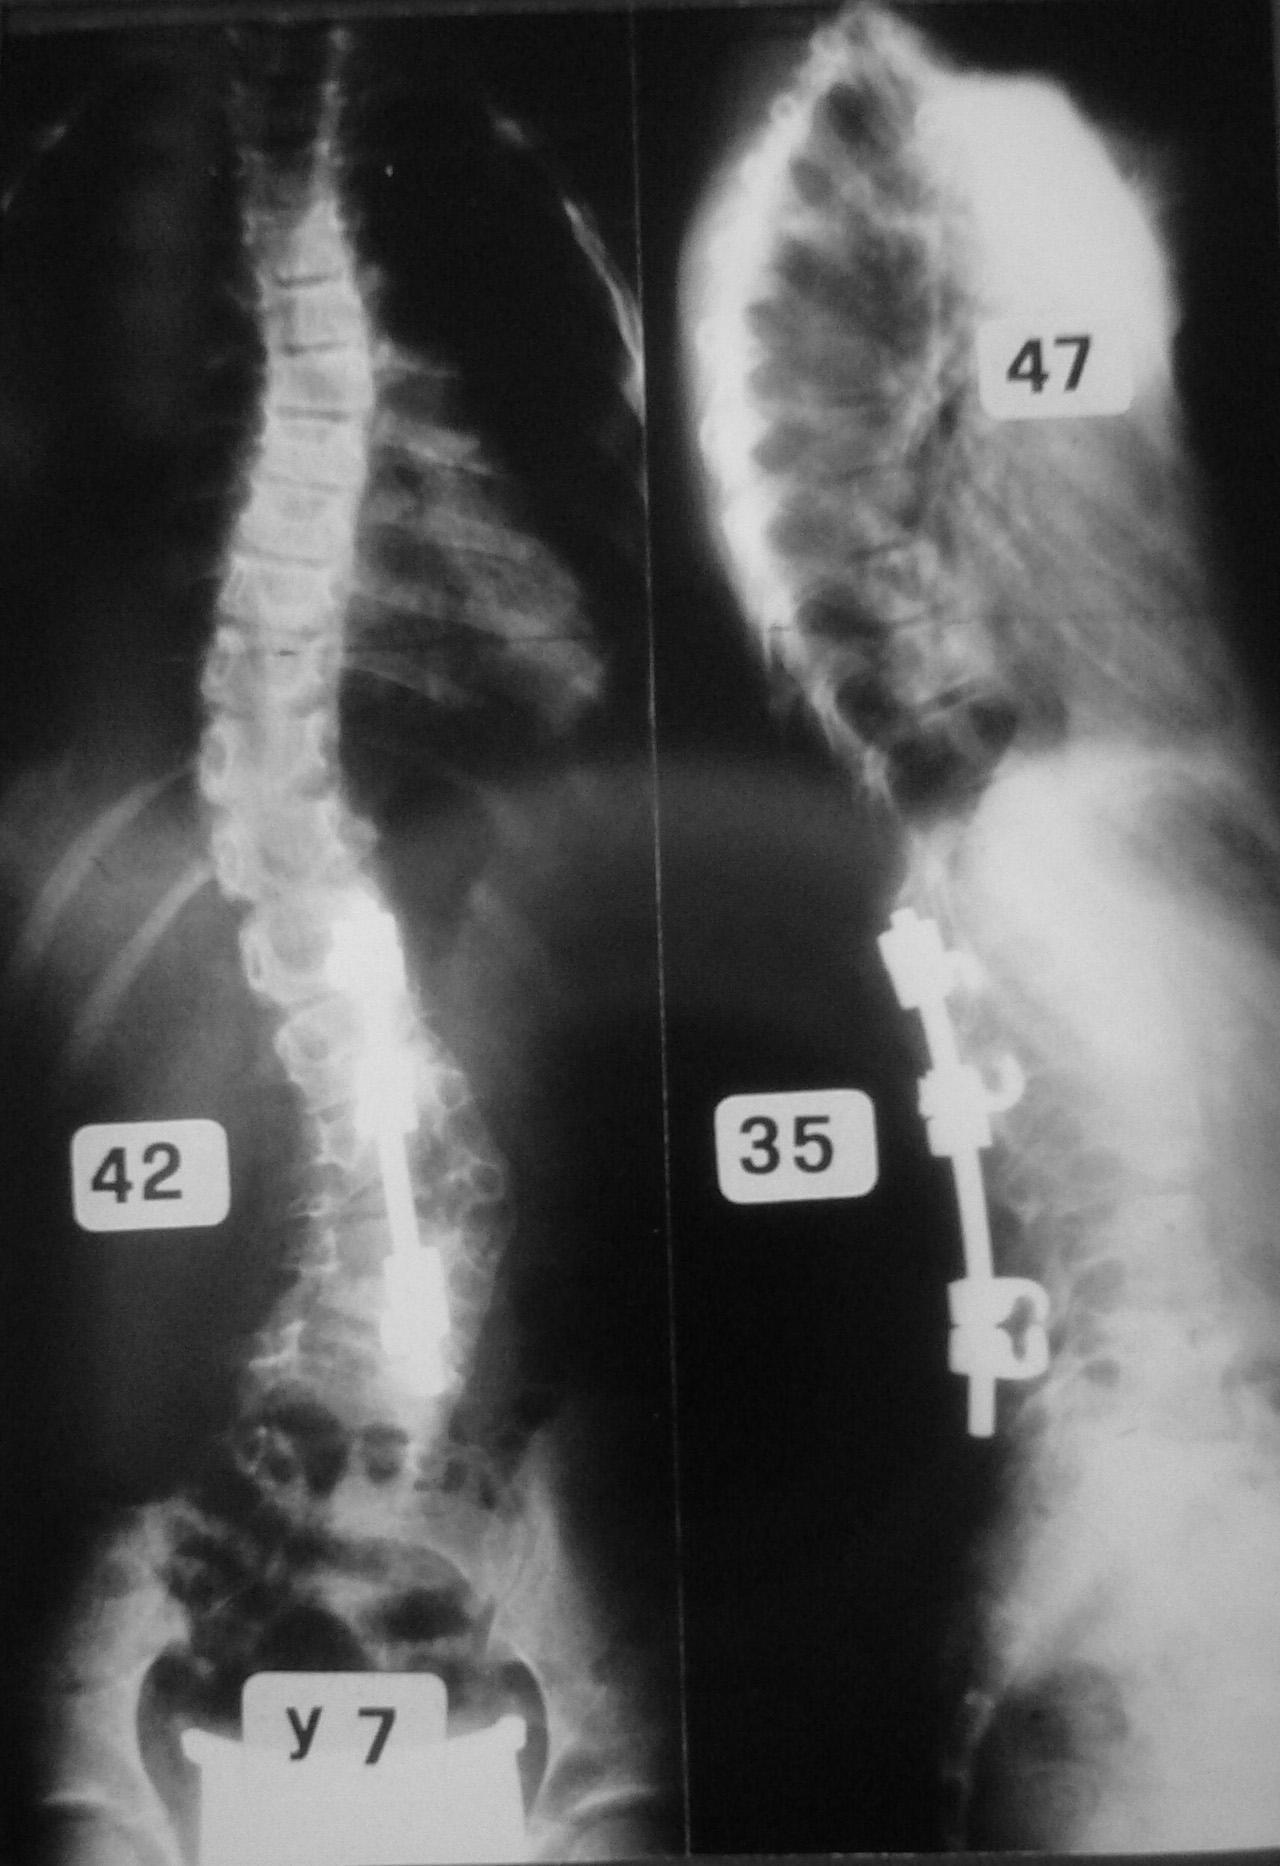

Il trattamento delle forme gravi di scoliosi idiopatica dell’adolescente, patologia più frequente nel sesso femminile, può richiedere un intervento chirurgico correttivo, che comprende una riduzione della deformità vertebrale, con apposizione di strumentario metallico, e la sua artrodesi, cioè la fusione dei metameri vertebrali interessati dalla curva. Il chirurgo vertebrale seleziona l’area da sottoporre ad intervento, per limitare una eccessiva rigidità a livello lombare, risparmiando il maggior numero di dischi intervertebrali caudali alla deformità (9,11). A volte, in presenza di gravi curve lombari, può essere però indispensabile estendere l’artrodesi a L4 o persino a L5. In questi casi è limitata la possibilità di flettere il tronco, e la forza del torchio addominale può essere diminuita (figura 3).

Occorre considerare inoltre come in un rachide sottoposto ad artrodesi vertebrale posteriore possa risultare impossibile l’accesso al canale vertebrale per l’esecuzione di una analgesia peridurale.